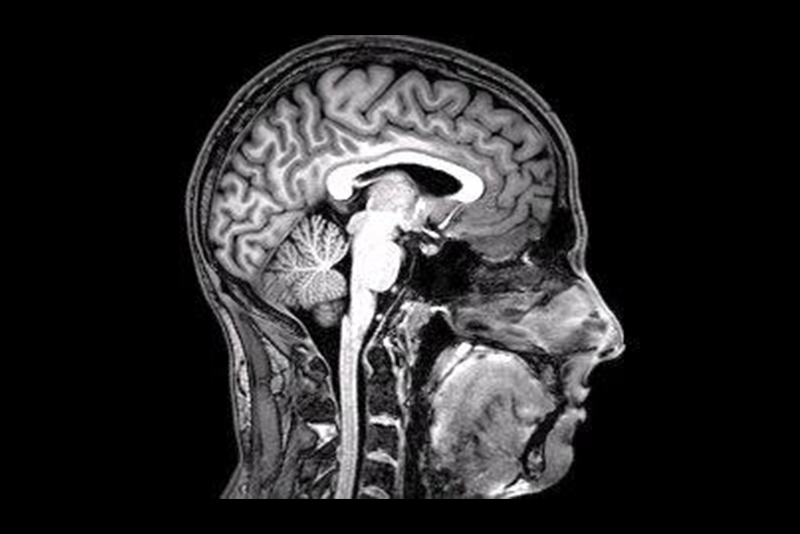

这并不奇怪。自从戈特弗里德·莱布尼茨(Gottfried Leibniz)提出一个基本而明显的观点以来,已经有300年了,即如果你能把人脑膨胀到一栋大楼那么大,然后走进去,你仍然无法在其中“定位”任何主观感知。即使有现代科学的帮助,也没有人能回答你是如何找到它们的——即使是在理论上。套用尼采的话来说,我们描述得越来越详细,但仍然没有解释任何东西。

康威·莫里斯举了脑积水的例子——这是一种被广泛报道的现象,患者似乎失去了90%的大脑,但至少在某些情况下,他们的功能几乎完全正常——以及“临终清醒”,即老年人或大脑受损的人在死前几小时突然恢复到完全清醒的意识。德国心理学家迈克尔·纳姆(Michael Nahm)和他之前的詹姆斯一样,也认为如果我们采用“过滤”的方法,像濒死体验和“转世事件”这样的边缘超自然现象可以被纳入主流。